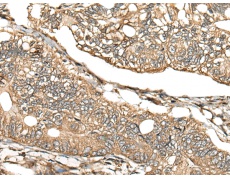

IHC positive control: |

Human gastric cancer |

30-150 |